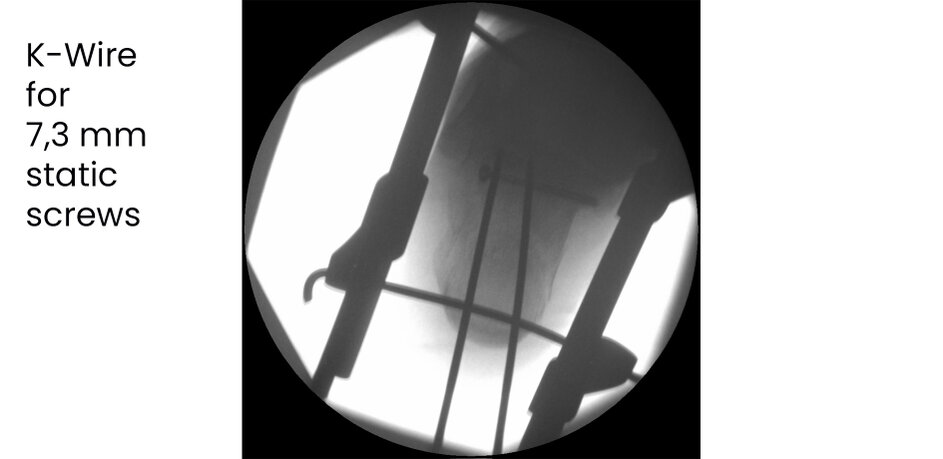

Case 17KL, male, 35y, surgery on day of trauma